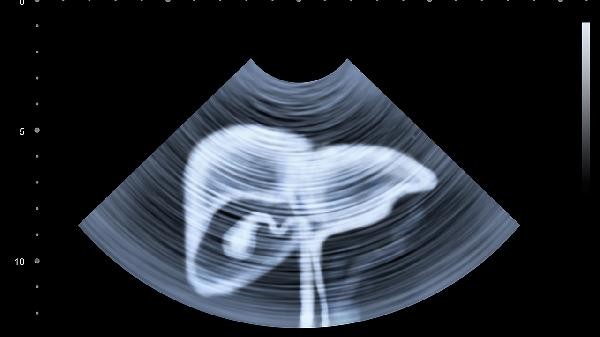

Repeated elevated transaminase levels are usually recommended for hepatitis C testing. Hepatitis C virus infection is one of the common causes of elevated transaminase levels, while other possible causes include fatty liver, drug-induced liver injury, alcoholic liver disease, etc. It is recommended to seek medical attention promptly to complete tests such as hepatitis C antibody and HCVRNA testing, and receive targeted treatment after identifying the cause. Repeated elevated transaminase levels may be associated with hepatitis C virus infection. The hepatitis C virus continues to attack liver cells, causing liver cell damage and transaminase release. The patient may experience symptoms such as fatigue, decreased appetite, and discomfort in the upper right abdomen. Diagnosis requires screening for hepatitis C antibodies and HCVRNA testing. If diagnosed with hepatitis C, antiviral drugs such as Sofosbuvir, Vepatasvir tablets, and Gecarevir, Pembrolizumab tablets can be used according to medical advice. In addition to hepatitis C, non-alcoholic fatty liver disease may also cause an increase in transaminase volatility. These patients are usually accompanied by metabolic abnormalities such as obesity and insulin resistance, and ultrasound examination shows hepatic fat infiltration. Treatment requires improving metabolic status through dietary control, weight loss, and exercise. Drug induced liver injury is common in people who have been taking liver toxic drugs such as acetaminophen tablets and anti tuberculosis drugs for a long time. After stopping the medication, transaminase levels can gradually recover.